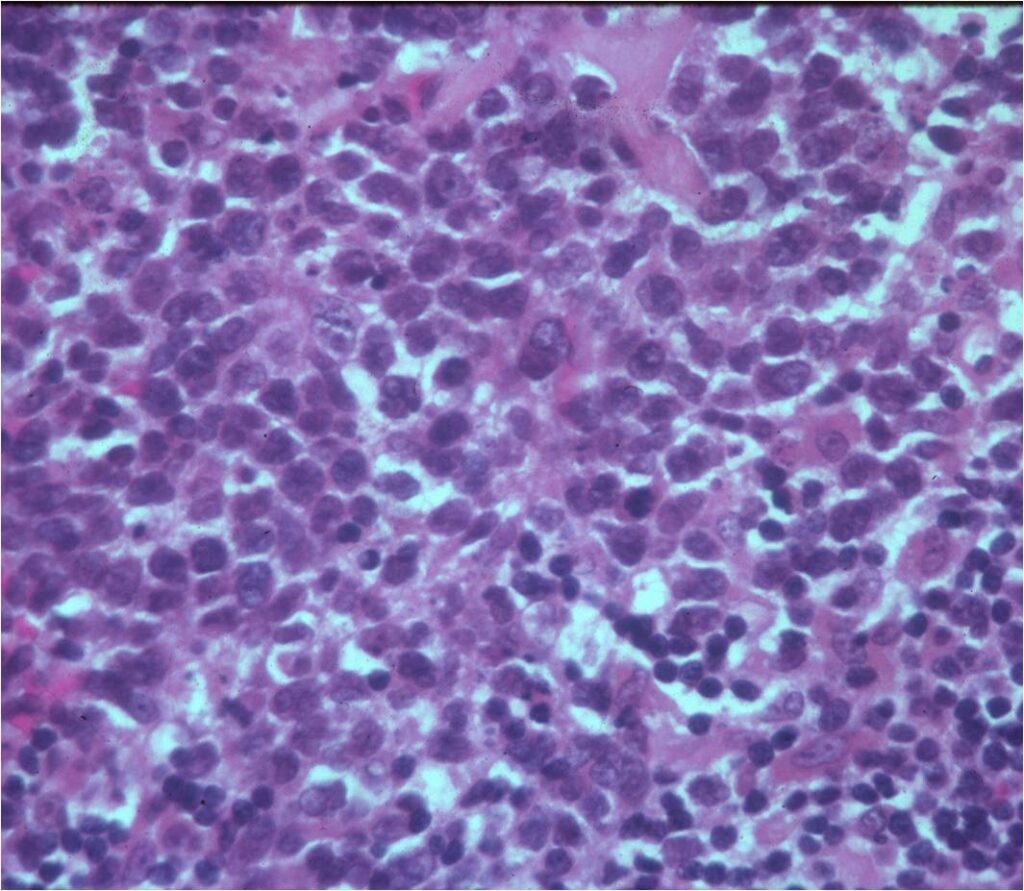

Microscopic Pathology

- Diffuse growth pattern

- Mixture of small lymphocytic cells and larger histiocytic components (Large Malignant B Cells in most cases)

- Cells and no matrix

- Nuclei

- Vary in shape and size

- Grooved vesicular nuclei

- Prominant nucleoli

- Cytoplasmic glycogen is absent

- Complex reticulin framework

- Prominent fibroblastic component

- CD5 and Leukocyte Common Antigen Positive

- CD3+ and CD45+ for B Cell Lymphoma; CD3+ for Rare T-Cell